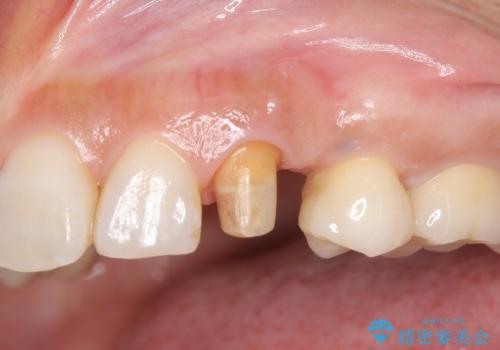

- 左上犬歯の一部が歯ぐきの中まで虫歯になっており、部分矯正をして歯を引っ張り出しました。(エクストリュージョン)

開始前

左:虫歯を除去したところ。遠心が歯ぐきより深い状態です。中:そのままかぶせようとすると、遠心が歯ぐきが腫れやすい状態です。右:エクストリュージョンをしたことで、遠心の歯ぐきの腫れが収まっていることがわかります。